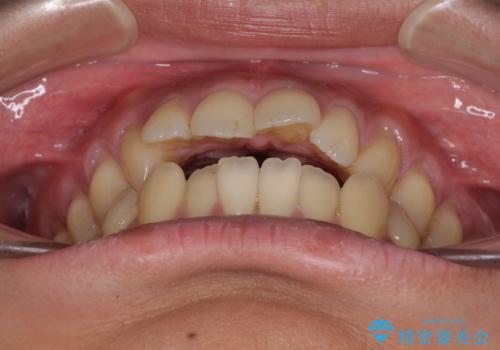

- 上下前歯の隙間と口元の出っ張った感じを気にして来院された患者様です。

上下の隙間は舌突出癖によるもので、またその癖により前歯が前方に出ている状態でした。

口元の出っ張りを改善するため、上下左右第一小臼歯4本を抜去し、ワイヤー装置にて矯正治療を行うこととしました。